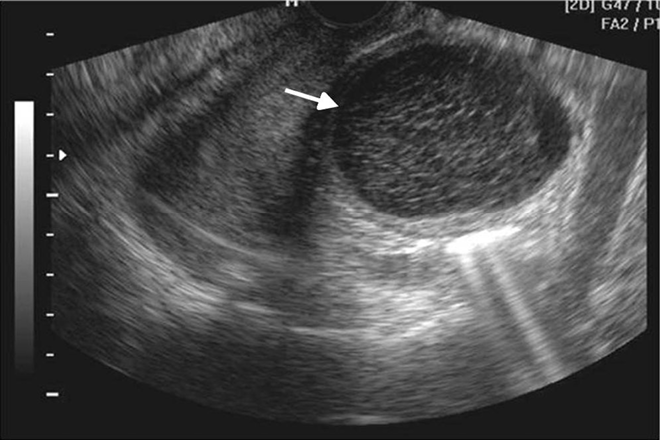

La evaluación de posibles predictores de cáncer de próstata para establecer un sistema de puntuación para repetir biopsias en hombres

En ésta ocasión la población de estudio se trata del continente asiático quienes por su gran diversidad en su estilo de vida en general cuentan con diferencias estadísticas significativas en comparación con el Occidente, independientemente de esto el realizar un puntaje adecuado como predictor para toma de biopsias en cáncer